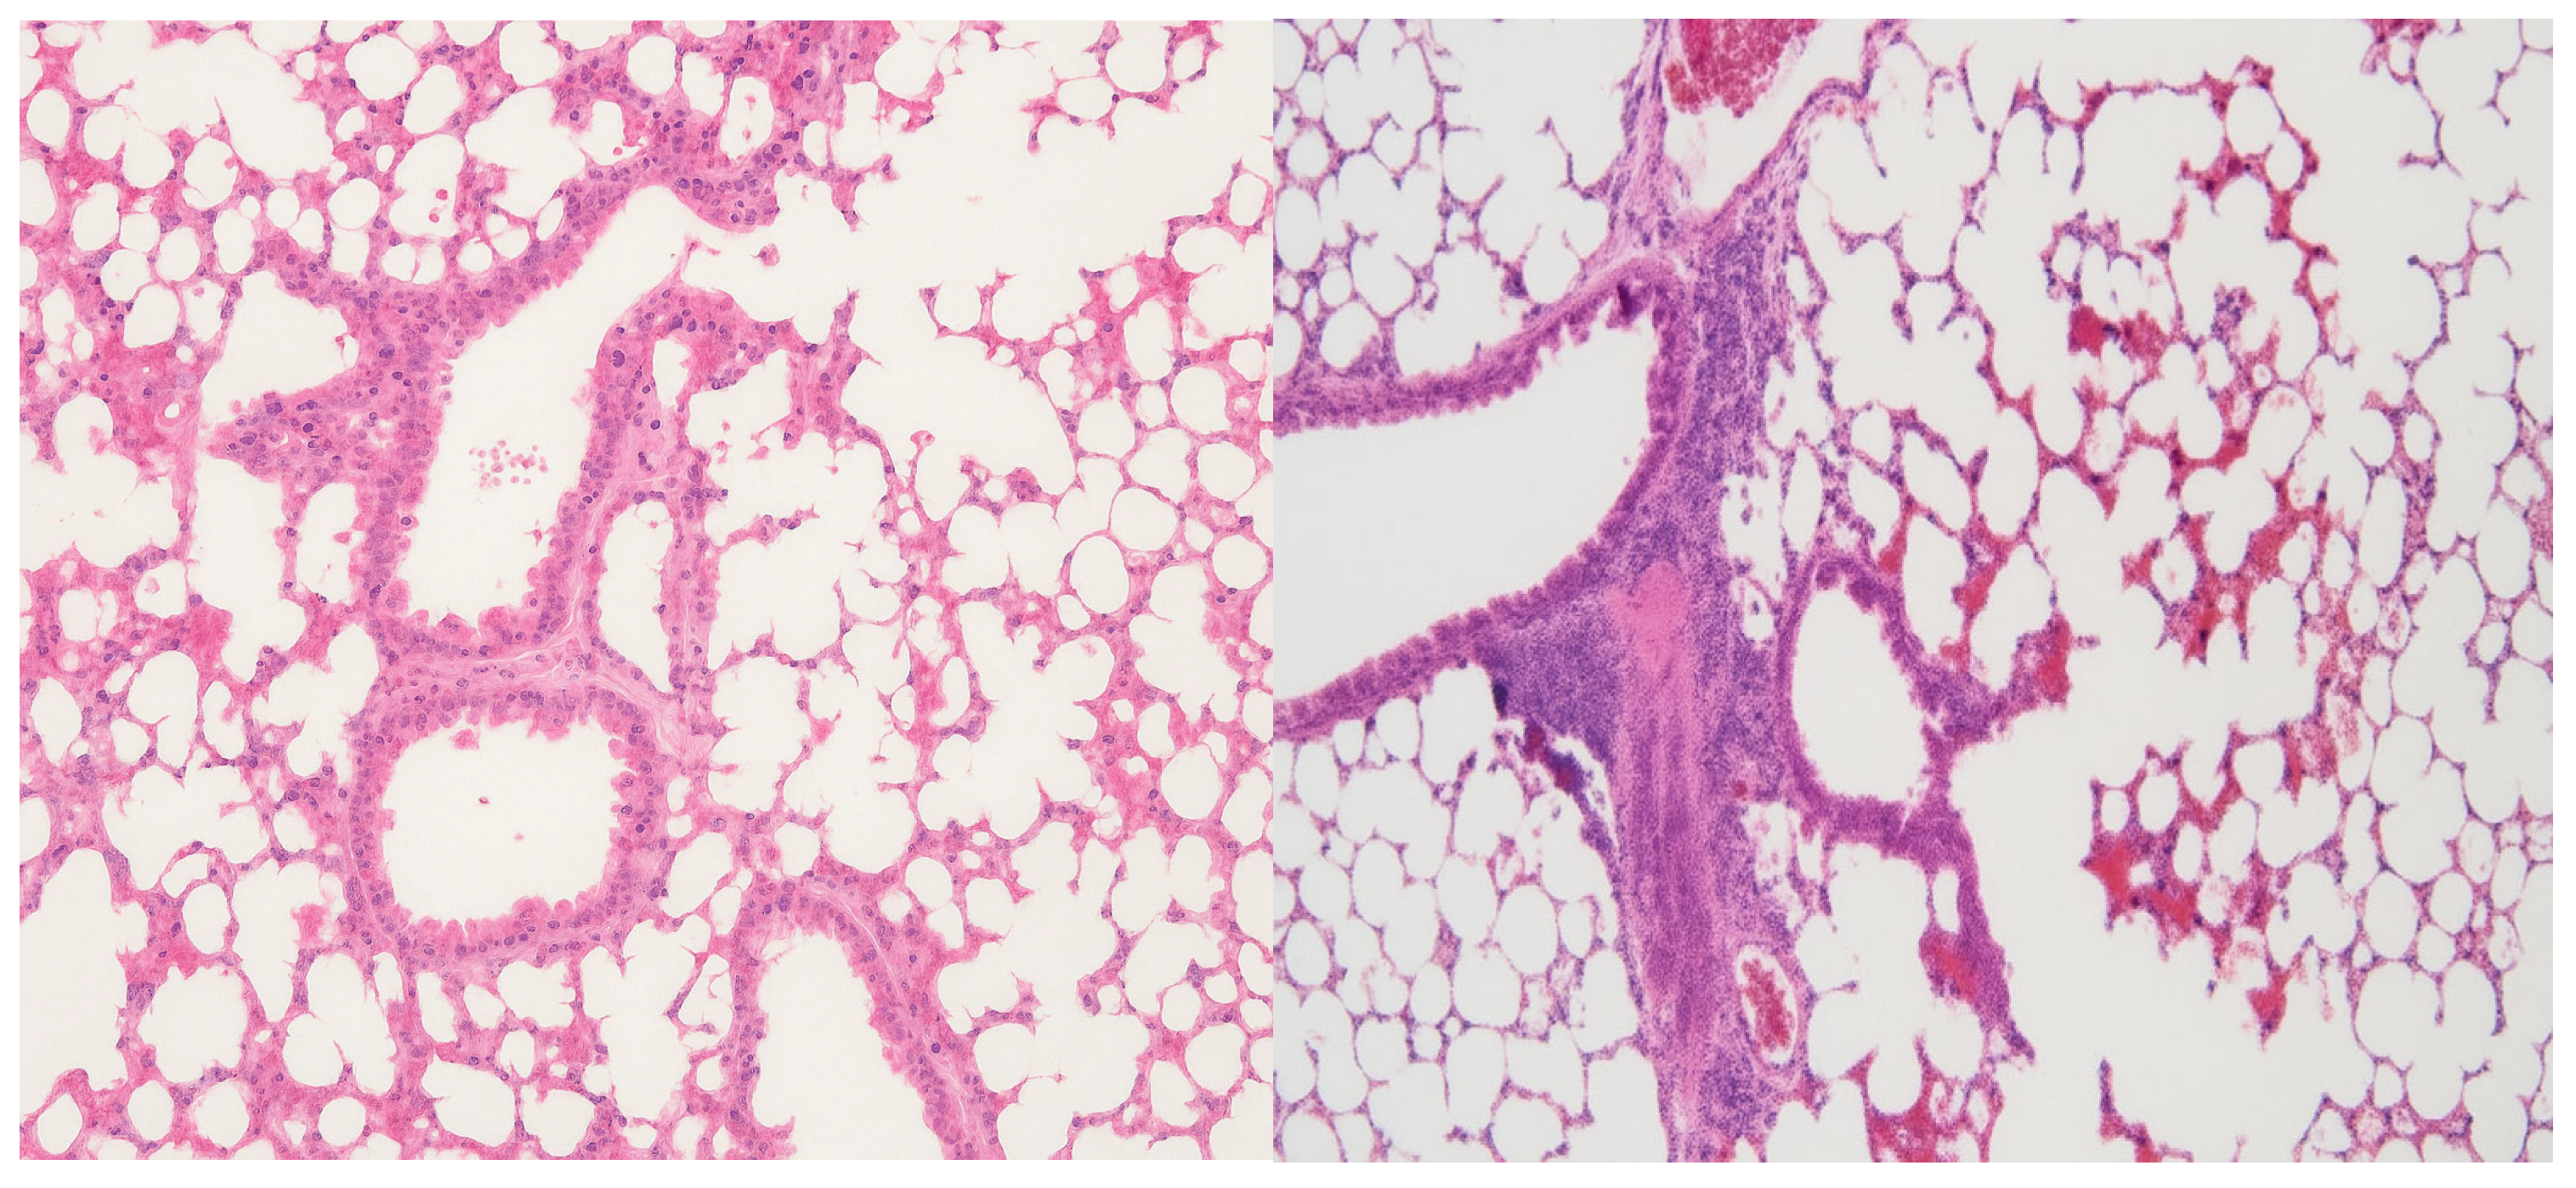

In the spleen, both the 10 mg/kg and 20 mg/kg groups preserved normal histological architecture (

Figure 1A). Active extramedullary hematopoiesis was present, involving erythroid, myeloid, and megakaryocytic precursors, which is consistent with physiological activity in murine spleen tissue. In contrast, the 50 mg/kg group exhibited multifocal amyloid deposits in the perifollicular zones (

Figure 1B). These deposits led to the compression and focal atrophy of adjacent splenic tissue, suggesting a dose-related accumulation of proteinaceous material potentially associated with nanoparticle clearance or chronic immune activation.